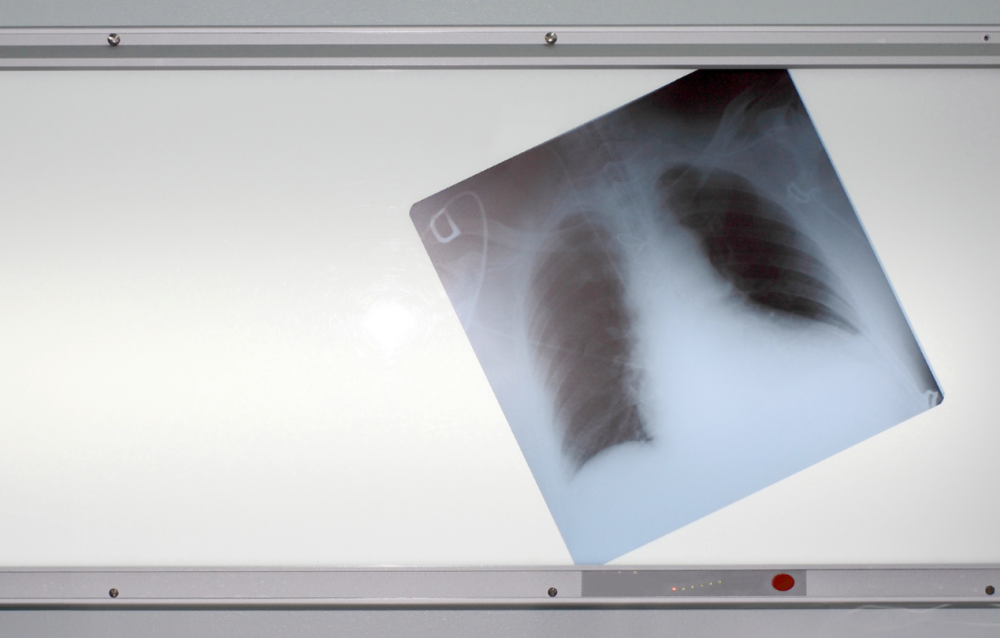

Курение признано основным фактором риска заболеваний легких, сердца и нервной системы.